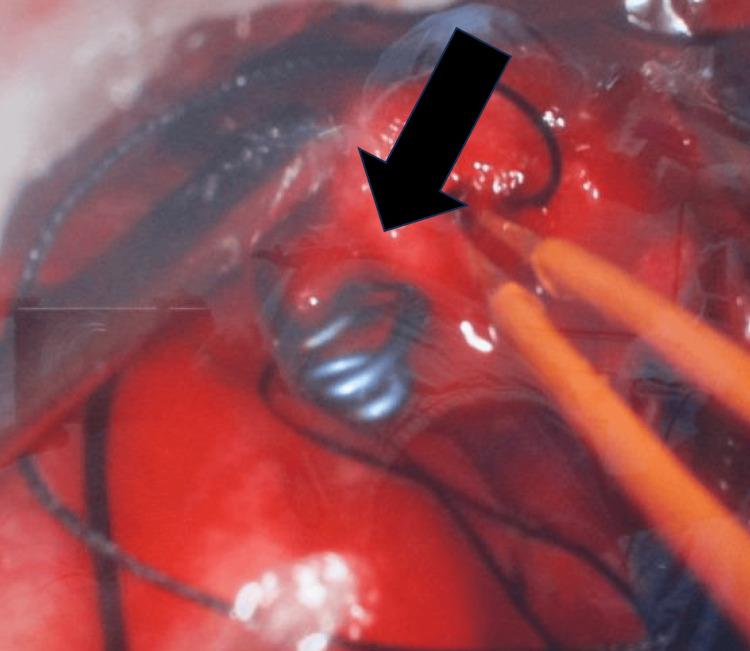

Intracranial aneurysms in pediatric populations are rare, with a distinct clinical profile compared to adult cases. This case report describes the clinical presentation, diagnosis, and treatment of a nine-month-old male with an intracranial aneurysm. The child presented with convulsions, a depressed sensorium, and subsequent neurological deficits. Initial imaging revealed subarachnoid hemorrhage, and further angiographic studies identified an aneurysm rupture from the parietal branch of the right middle cerebral artery. The patient underwent successful neurosurgical intervention, including right craniotomy and aneurysm clipping. Post-operative recovery was marked by gradual neurological improvement and the absence of further seizures. This case underscores the importance of prompt diagnostic imaging and surgical management in pediatric intracranial aneurysms, contributing to favorable outcomes despite the rarity of the condition in this age group.

小儿颅内动脉瘤较为罕见,与成人病例相比具有独特的临床特征。本病例报告描述了一名9个月大患有颅内动脉瘤男性患儿的临床表现、诊断及治疗过程。该患儿出现惊厥、意识不清,随后出现神经功能缺损。初始影像学检查显示蛛网膜下腔出血,进一步血管造影研究确定为右大脑中动脉顶叶分支的动脉瘤破裂。患者接受了成功的神经外科手术干预,包括右开颅手术和动脉瘤夹闭术。术后恢复表现为神经功能逐渐改善且未再发生惊厥。本病例强调了小儿颅内动脉瘤及时进行诊断性影像学检查和手术治疗的重要性,尽管该疾病在这个年龄组中罕见,但仍有助于取得良好预后。